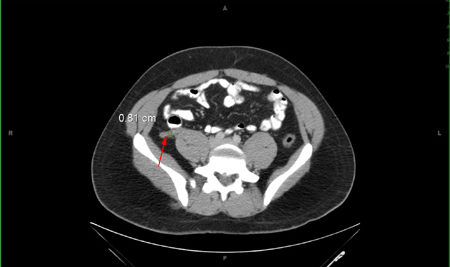

Em crianças com dúvida diagnóstica e resultados de ultrassonografia inconclusivos, uma técnica de imagem de segunda linha (TC ou RNM) deve ser usada com base na disponibilidade e experiência local.[7][Figure caption and citation for the preceding image starts]: Tomografia computadorizada (TC) abdominal – espessamento do apêndice.Nasim Ahmed, MBBS, FACS; usado com permissão [Citation ends].com.bmj.content.model.Caption@35252a12

Espessamento e dilatação da parede, bem como alterações inflamatórias nos tecidos adjacentes, são achados adicionais observados em uma TC de abdome e pelve.[69]

A TC do apêndice é cada vez mais usada como teste diagnóstico inicial para apendicite aguda, e é prática rotineira nos EUA solicitar uma TC para pacientes que comparecem ao pronto-socorro com sintomas de apendicite aguda.[29] A Infectious Diseases Society of America (IDSA) oferece uma recomendação condicional para TC abdominal como modalidade de imagem inicial para diagnosticar apendicite aguda.[53]​ A TC também é indicada em quadros atípicos.[33][54]

apêndice anormal (diâmetro >6 mm) identificado ou apendicolito calcificado observado em associação com inflamação periapendicial, acúmulo de gordura